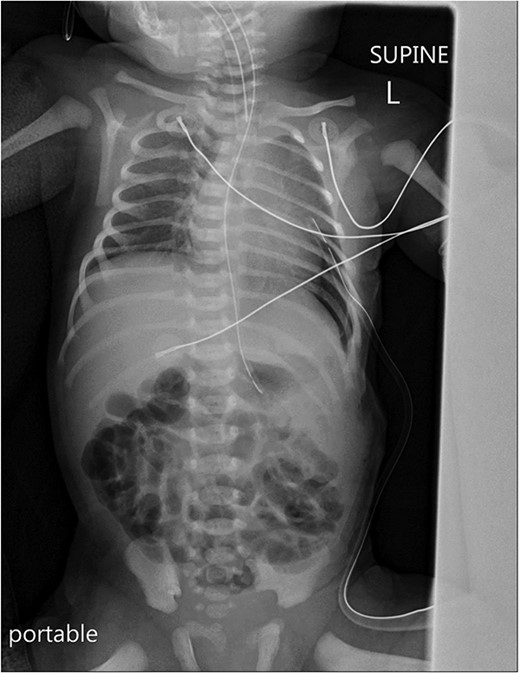

A chest X-ray revealed a left-sided diaphragmatic herniation of bowel loops into the left hemithorax along with displacement of the cardiac shadow to the right (Fig. 1). Nasogastric and endotracheal tubes were also inserted. Umbilical arterial and venous catheter insertion was attempted but failed and removed the next day.

A portable X-ray photo of the chest, abdomen and pelvis shows the right mediastinal shift, total collapse of the left lung, partial collapse of the right lung and air-filled structures (bowel loops) extending from the abdomen into the chest.